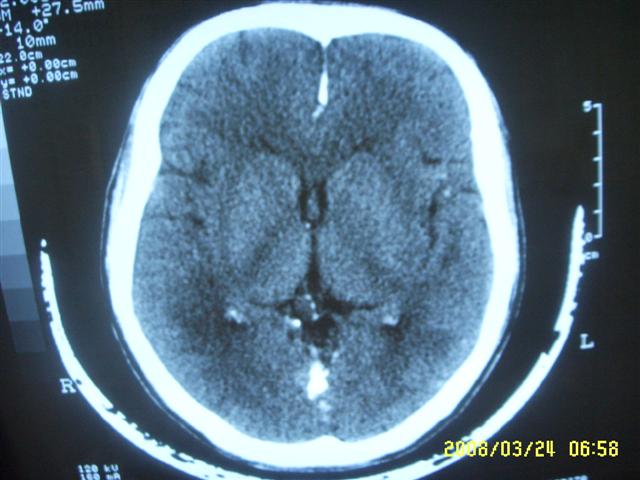

以下是引用dyqct在2008-4-2 20:09:00的发言:[br]考虑为:神经纤维瘤病(nf1型)。建议增强进一步检查。